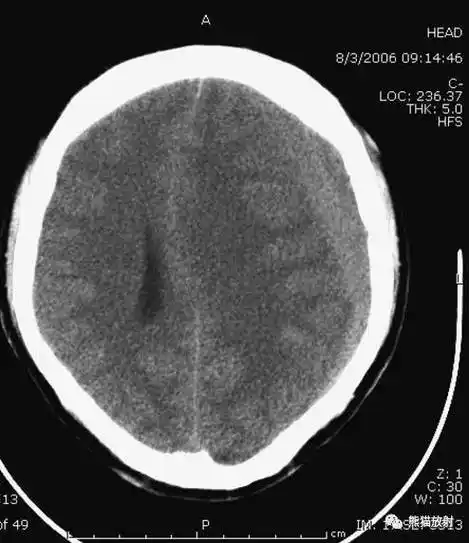

头颅CT